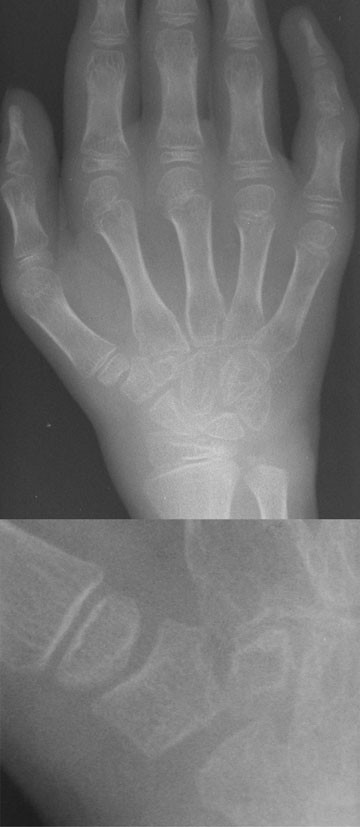

Photos. Clinical radiology of the horse, blackwell science ltd., massachusetts. Although there is great individual variability, approximate ossification times are as follows 1

The carpal bones are the eight small bones that make up the wrist (or carpus) that connects the hand to the forearm. The term carpus is derived from the latin carpus and the greek καρπός (karpós), meaning wrist. Carpal kinematics during functional tasks: Specialized cells that secrete bone matrix.